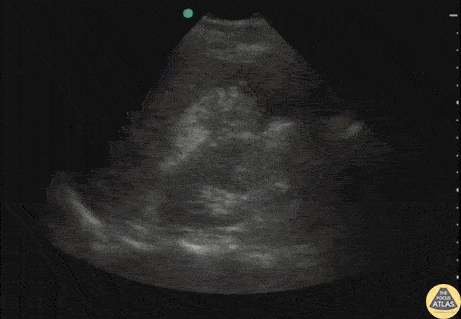

Pt struck by car while riding bike. Perihepatic view on FAST exam revealed a perforated viscus (gastric rupture). Note the free air within the fluid. Image courtesy of Robert Jones DO, FACEP @RJonesSonoEM Director, Emergency Ultrasound; MetroHealth Medical Center; Professor, Case Western Reserve Medical School, Cleveland, OH View his original post here.